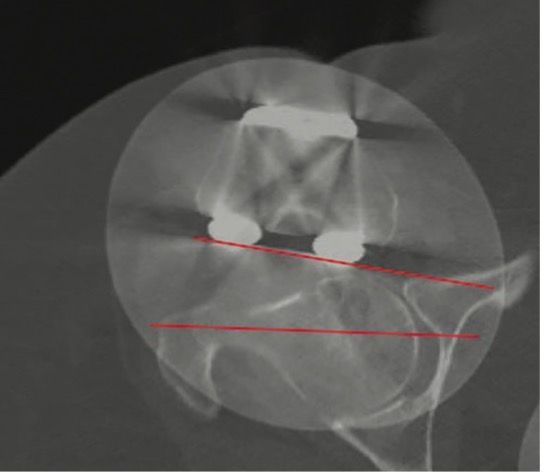

A bilateral CT scan is essential for obtaining official confirmation of rotational problems with the femoral and/or tibial components. In TKA patients with PFI the relevant measurement is the rotational alignment of the components relative to the landmarks of the knee. Malpositioning of the components must be measured by the posterior condylar angle for the femur (posterior condylar line to epicondylar axis) and anterior tibia tubercle angle for the tibia (AP line of tibia surface to TTA – Tibia tubercle to PCL line). The combined internal rotation of the tibia and femur component is directly correlated to the degree of patellofemoral instability (1–4° combined component rotation = lateral tracking and tilting; 4–8° = subluxation; >8° = early patellar dislocation with risk of loosening).[11]

These patients have total or partial lateral dislocation of the patella (Fig. 1). The cause is rotational malalignment of the femur and/or tibia implant (Fig. 2) or severe torsional limb malalignment with increased femur anteversion or excessive tibia internal rotation or both.